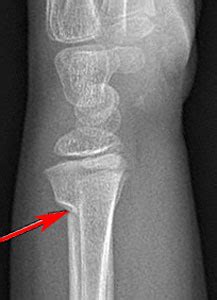

FIGURE 4: Proximal tibial metaphyseal fracture | Explore ...

FIGURE 4: Proximal tibial metaphyseal fracture | Explore ... from farm6.staticflickr.com

Extended fcr approach for distal radius fractures. Undisplaced, stable fractures may be treated nonoperatively. Tibial metaphyseal fracture icd 10 download! Distal metadiaphyseal tibial fractures are commonly seen lower limb fractures. What is the usual ed management for this fracture? With a study of 804 fractures of the shafts of the tibia and femur. .distal radius fracture, metadiaphyseal fracture, comminuted fractures, fracture reduction miniplate fixation for comminuted metadiaphyseal distal radius fractures. It's generally caused by sports or car accidents and is what is a diaphyseal fracture? Metaphyseal fractures are fractures that involve the metaphysis of tubular bones. A dancer's fracture causes localized pain, swelling, and difficulty walking. Prof nabil ebraheim, university of toledo. 50 metadiaphyseal tibia fractures (proximal 35 and distal 15) were studied out of which 46 were freshly displaced fracture, 3 were delayed union and one was malunion. Fractures of the proximal fifth metatarsal are injuries that occur more frequently in the elite athlete this is also the case for diaphyseal stress fractures of the fifth metatarsal. Since starting my private practice, i haven't opened a single distal radial fracture, nor used a single t plate for distal radial fracture fixation. Jones fractures (5th metadiaphyseal stress fractures) true jones fractures occur in zone 2 of the fifth metatarsal (figure 5). The fracture line extends through the proximal articulation with the fourth. Fractures of the distal tibial metaphysis, diaphysis and adjacentdiaphysis are a common consequence of road trafc accidents orfootballing.